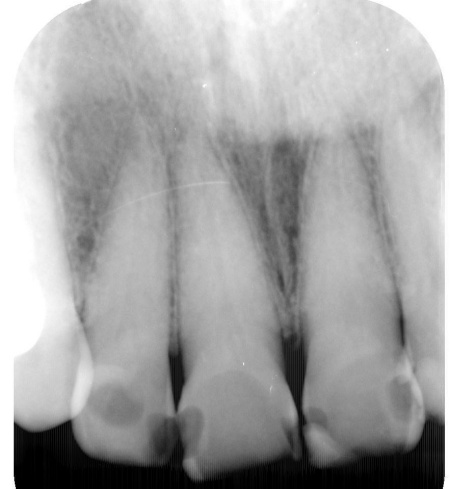

レントゲン撮影をして詳しく検査したところ、複数の小さな虫歯が見られました。

また右上奥歯には、歯根の先に炎症が起きて膿が溜まる根尖性(こんせんせい)歯周炎が認められます。

①小さな虫歯を発症している部位には、虫歯の除去後に保険診療のプラスチック材料「コンポジットレジン(CR)」を充填する治療を行います。

まず、虫歯部分を丁寧に取り除いてから歯の形を整え、CRを詰めてしっかりと研磨します。